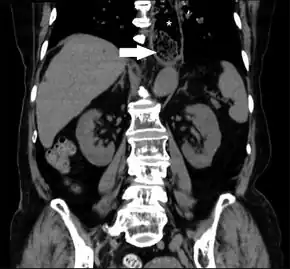

- Computed tomography